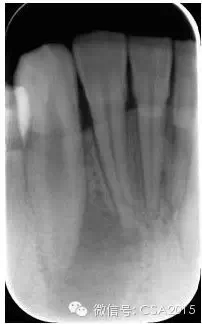

7 根管充填

封閉整個(gè)根管系統(tǒng)、堵塞主根管和側(cè)副根管出口、防止微生物和液體的滲漏。無(wú)論是側(cè)方加壓法還是垂直加壓法,應(yīng)做到根管充填致密,根管充填后X線片上無(wú)根管腔隙,也不能超出根尖孔。